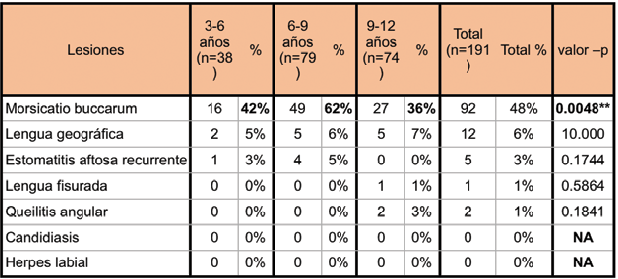

La lesión identificada con mayor frecuencia fue Morsicatio buccarum (Fig 2) con 92 casos (48%) para el total de la muestra. Luego le siguen Lengua geográfica (6%) (Fig 3), Estomatitis aftosa recurrente (3%) (Fig 4), Queilitis angular (1%) (Fig 5) y Lengua fisurada (1%) (Fig 6).

No se encontraron casos de Candidiasis ni Herpes labial. Las lesiones y variantes de la normalidad encontradas que se incluyeron dentro de la categoría “Otras” fueron: fosita comisural, lengua saburral, manchas melánicas, trauma de comisuras, trauma de labios, trauma por aparatos removibles, frenillo lingual corto, trauma de lengua, cicatriz de mucocele, ulceración de encía, verruga labial, cicatriz de afta mayor, papilas caliciformes hiperplásicas, trauma de piso de boca, trauma de encía, lesiones aftoides, pápulas, fisura de bermellón, costra de bermellón, melanoplaquia, erosión de mejilla, erosión de labio, cicatriz de ulceración, fístula y trauma palatino; las cuales no formaban parte de los objetivos del estudio.

La lesión identificada con mayor frecuencia en ambos géneros fue Morsicatio buccarum y la diferencia entre ambos resulto no significativa. Estomatitis aftosa recurrente fue la única lesión observada con más frecuencia en el género femenino (valor-p = 0.0207, prueba exacta de Fisher), con 5 casos versus ninguno en el masculino.

Considerando el tipo de dentición del sujeto, se vio que Morsicatio buccarum fue la lesión más frecuente en los tres tipos de dentición (T = 43%, M = 52% y P = 20%), observándose diferencias significativas Chi-cuadrado=6,2136 , valor-p = 0,0447*.

Se encontraron diferencias significativas (valor-p = 0.0048**) entre la prevalencia de Morsicatio buccarum en los tres grupos de edad, mostrando mayor incidencia en el grupo de 6-9 años (62%), seguido por el grupo de 3-6 (42%), y por último el de 9-12

años (36%) (Tabla 4).